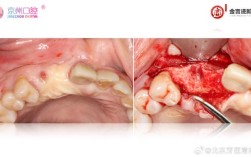

- 准备: 常规消毒、麻醉,翻开牙龈瓣暴露骨缺损区域。

- 处理骨缺损: 清理骨缺损区,可能需要植骨(骨粉)来填充空间。

- 放置骨粉: 将骨颗粒填入缺损区域。

- 放置膜: 将引导骨再生膜覆盖在骨粉表面,覆盖范围需超出缺损区。

- 固定膜: 使用专用工具,将1-3颗(根据缺损大小和位置)膜钉穿过膜的边缘,将其牢固地固定在下方的骨面上,确保膜没有皱褶和过度张力。

- 缝合: 将牙龈瓣复位缝合,关闭伤口。